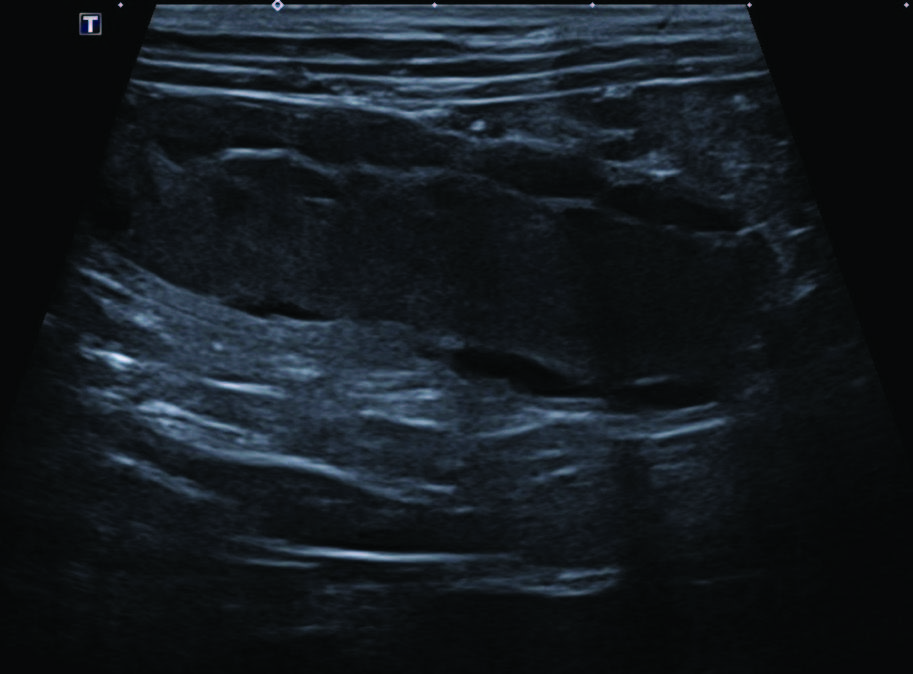

超声可见双子宫角中度扩张(最大径17 mm),腔内为不移动的高回声内容物,壁不规则,并见多个壁内卵圆形无回声灶(图2)。

图2. 使用微凸探头B模式,在左侧卧位进行的腹部超声纵切面检查。图像左侧为头侧。右侧子宫角中度扩张,腔内为不移动的高回声内容物,壁不规则,并可见多个壁内卵圆形无回声病灶。